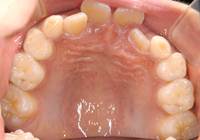

治療前:上顎

治療後:上顎

治療中:上顎